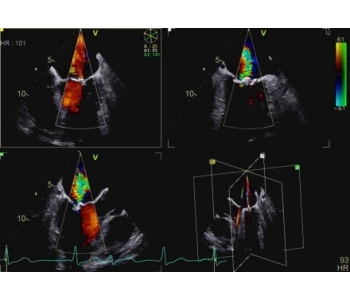

The 4D ICE NUVISION Catheter offers real-time volumetric imaging, a 90x90 field of view, 4D color Doppler flow capabilities, and an independently rotating tip, making it an ideal choice for left atrial appendage closure (LAAC) procedures.